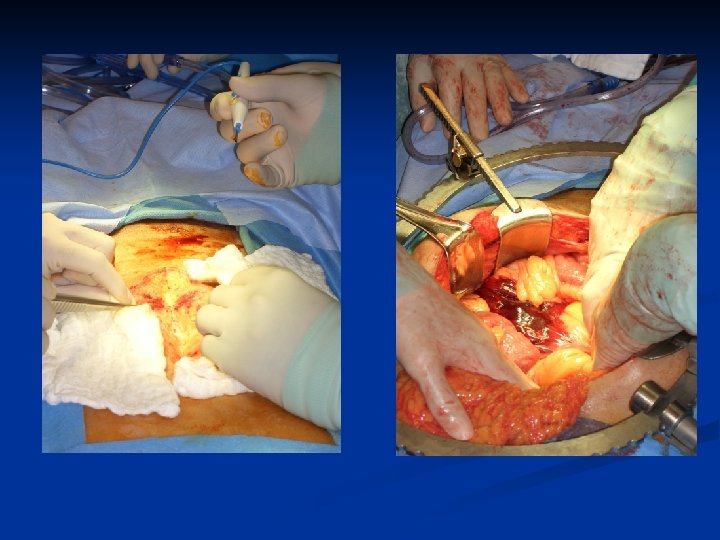

On Route to OR n n ABC Chest x-ray, Pelvis x-ray IV access Resuscitation n n n What is the goal? Group and Match Notify OR, Surgeon, Anaesthesia Request OR equipment Consent Antibiotics

Case 1: Learning Points Recognize Shock n Hemodynamically unstable = OR n Role of FAST, DPL n Permissive hypotension in resuscitation until bleeding controlled n